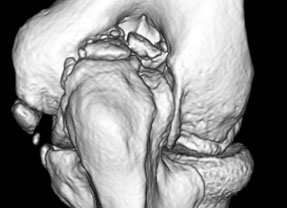

CTとはX線を使って骨の断面像を作成する検査法で、レントゲン写真より何倍もの情報を正確に得ることができることができます。また3次元画像で人体の構造を立体的に表示できるようになり、実際の診断や患者様への説明においても大変わかりやすいものとなっています。実際に検査を受けている時間は10分程度ですので、精密検査でありながら、すぐに施行することができる”敷居の低い”検査として、日夜大活躍しています。